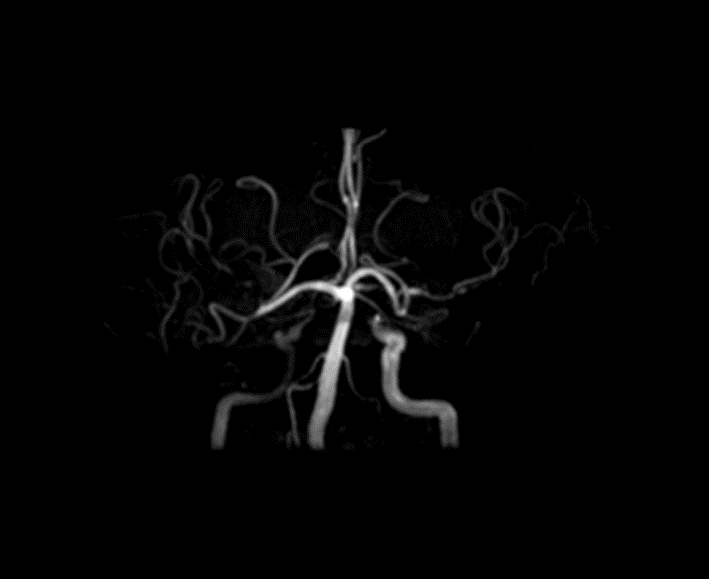

Objective To summarize diagnostic and differentialdiagnostic approaches for initial detection of moyamoya disease (MMD) using carotid ultrasound (CAU). Methods We report two patients who were first diagnosed with MMD by CAU and summarize the diagnostic reasoning and differential considerations. Relevant literature was reviewed to contextualize these findings. Results Case 1: A 57-year-old female presented with a >10 year history of dizziness and headache with recurrence over 3 days. CAU showed a reduced diameter of the left internal carotid artery (ICA), decreased flow velocity, and a lower resistance index, raising suspicion for severe intracranial stenosis or occlusion and prompting clinical exclusion of MMD. Magnetic resonance angiography (MRA) confirmed severe stenosis of the left ICA with absent distal branches and multiple small abnormal vascular networks in the left suprasellar region, consistent with MMD. Case 2: A 23-year-old male presented with dizziness for >1 year and transient right upperlimb weakness for 1 day. CAU and transcranial color Doppler (TCCD) showed a narrowed right ICA with reduced flow velocity and increased resistance index, suggesting chronic occlusion of the right middle cerebral artery and stenosis of the left middle cerebral artery, raising the possibility of MMD. MRA demonstrated an indistinct right ICA and right middle cerebral artery and narrowing of the left middle cerebral artery. On followup, the patient was diagnosed with MMD. Conclusion When CAU reveals a small internal carotid artery diameter accompanied by slowed flow velocity, clinicians should perform a comprehensive evaluation-including TCCD and further vascular imaging-to avoid missed or incorrect diagnoses of MMD.